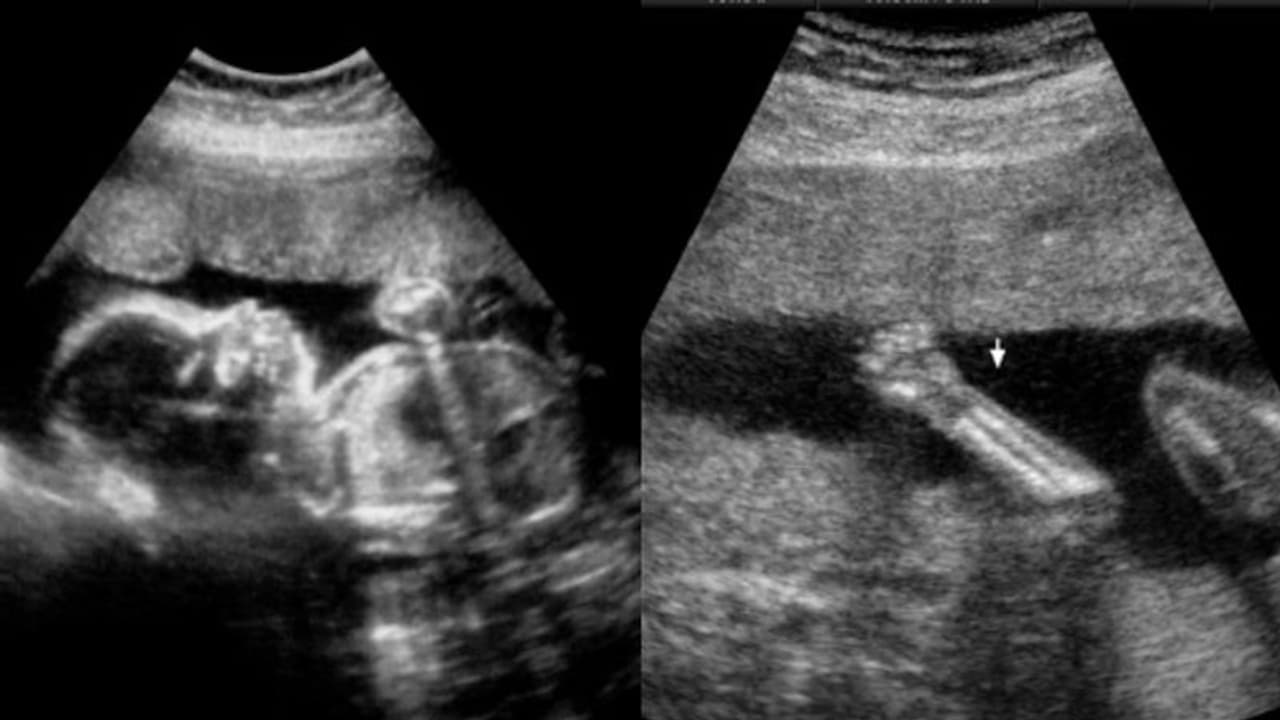

തിരുവനന്തപുരം: ഗർഭസ്ഥശിശുവിന്റെ വൈകല്യം കണ്ടെത്തുന്നതിൽ വീഴ്ച വരുത്തിയ സ്വകാര്യ ആശുപത്രി പലിശ സഹിതം 82 ലക്ഷം രൂപ നഷ്ടപരിഹാരമായി നല്കാൻ സംസ്ഥാന ഉപഭോക്തൃ കമ്മീഷന്റെ ഉത്തരവ്. ഭ്രൂണത്തിന് അരക്ക് താഴോട്ട് വളർച്ചയില്ലെന്ന് സ്കാനിങ്ങിലൂടെ കണ്ടെത്തുന്നതിൽ പരാജയപ്പെടുകയും സ്കാനിങ് റിപ്പോർട്ടിൽ കൃത്രിമം കാണിക്കുകയും ചെയ്ത ആശുപത്രി അധികൃതർക്ക് രൂക്ഷ വിമർശനത്തോടെയാണ് കമ്മീഷൻ്റെ തീരുമാനം. ഇല്ലാത്ത കാലുകളുടെ തുടയെല്ലിന്റെ നീളം ആണ് സ്കാനിംഗ് റിപ്പോർട്ടുകളിൽ രേഖപ്പെടുത്തിയിരിക്കുന്നത്. വിദേശ മലയാളി ദമ്പതികളായ ജയേഷ്, രശ്മി ദാസ് എന്നിവരുടെ പരാതിയിലാണ് 8 വർഷത്തിനു ശേഷം വിധി വന്നിരിക്കുന്നത്.

പത്തനംതിട്ടയിലെ സ്വകാര്യ ആശുപത്രിക്ക് എതിരെയായിരുന്നു ദമ്പതികളുടെ പരാതി. ഗർഭിണിയായി പത്ത് ആഴ്ച പിന്നിട്ടപ്പോഴാണ് രശ്മി നാട്ടിലെ ആശുപത്രിയിൽ ചികിത്സ തേടിയത്. തുടർന്നുള്ള ആഴ്ചകളിൽ സ്കാനിങ്ങുകൾ നടത്തിയെങ്കിലും ഒന്നിലും ഗർഭസ്ഥ ശിശുവിൻ്റെ വൈകല്യത്തെക്കുറിച്ച് ഡോക്ടർമാർ അറിഞ്ഞിരുന്നില്ല. യുവതിയെ വിശദമായ അനോമലി സ്കാനിങ്ങിനു വിധേയയാക്കിയതുമില്ല. 2015 ജനുവരി 10ന് സിസേറിയനിലൂടെ രശ്മി ആൺകുഞ്ഞിന് ജന്മം നൽകി. അപ്പോഴാണ് നവജാത ശിശുവിന് അരയ്ക്ക് താഴോട്ട് വളര്ച്ചയില്ലെന്ന് തിരിച്ചറിഞ്ഞത്. ശിശുവിന് ഇടുപ്പെല്ലും കാലുകളും ഇല്ലായിരുന്നു.

സ്കാനിങ്ങിൽ പ്രത്യേകിച്ച് തകരാറൊന്നും കണ്ടെത്താൻ കഴിയാഞ്ഞത് കൊണ്ടാണ് വിശദമായ അനോമലി സ്കാനിംഗ് നടത്താഞ്ഞതെന്നാണ് കുറ്റാരോപിതരായ ഡോക്ടര്മാരായ കെന്നി എ തോമസും പ്രീത ബിജുവും വാദിച്ചത്. അനോമലി സ്കാനിംഗ് നടത്താഞ്ഞത് ആശൂപത്രിയുടെ വീഴ്ചയായി കമ്മീഷൻ കണ്ടെത്തി. മാത്രമല്ല റേഡിയോളജിസ്റ് നടത്തേണ്ട സ്കാനിംഗ് അതിൽ പ്രാവീണ്യമില്ലാത്ത ഒരു ഡോക്ടറാണ് ചെയ്തത്. അമ്നിയോട്ടിക് ഫ്ലൂയിഡിന്റെ കുറവുണ്ടായത് കൊണ്ടാണ് വൈകല്യം അറിയാൻ പറ്റാഞ്ഞതെങ്കിൽ ഫ്ലൂയിഡിന്റെ കുറവ് സ്കാനിംഗ് റിപ്പോർട്ടിൽ രേഖപ്പെടുത്തേണ്ടതായിരുന്നു. ശിശുവിന്റെ ചലനത്തെക്കുറിച്ചു യാതൊരു കുഴപ്പങ്ങളും റിപ്പോർട്ടുകളിൽ പറഞ്ഞിട്ടില്ല. ഏറ്റവും ഗുരുതരമായ വീഴ്ച കാലുകൾ ഇല്ലാത്ത ശിശുവിന്റെ തുടയെല്ലിന്റെ നീളം റിപ്പോർട്ടുകളിൽ രേഖപ്പെടുത്തിയിരുന്നു എന്നതാണ്.

ആശുപത്രിയുടെ കൃത്യവിലോപം കൊണ്ട് കുഞ്ഞിനും മാതാപിതാക്കൾക്കും ജീവിതം ദുരിതമായെന്ന് കമ്മീഷൻ അഭിപ്രായപ്പെട്ടു. യുവതിക്ക് നാല് മാസമായപ്പോള് നടത്തിയ സ്കാനിങ്ങിൽ ഗര്ഭസ്ഥശിശു ആരോഗ്യവാനാണെന്നും പറഞ്ഞിരുന്നു. കൃത്യമായ അനോമലി സ്കാനിംഗ് നടത്താത്തതിനാല് ഭ്രൂണത്തിന് അരയ്ക്ക് താഴോട്ട് വളര്ച്ചയില്ലെന്ന വിവരം കണ്ടെത്തുന്നതില് ആശുപത്രി അധികൃതര് പരാജയപ്പെട്ടു എന്ന് കമ്മീഷൻ പറഞ്ഞു. അൾട്രാസൗണ്ട് സ്കാനിങ് ഫലങ്ങൾ 100% കൃത്യമാണെന്ന് വിശ്വസിക്കാൻ കഴിയില്ലെന്നും മറ്റ് പല ഘടകങ്ങളെയും ആശ്രയിച്ചിരിക്കുന്നതിനാൽ എല്ലാ വൈകല്യങ്ങളും കണ്ടെത്താനാകില്ലെന്നുമാണ് സെന്റ് ലൂക്ക് (ന്യൂ ലൈഫ് ഫെർട്ടിലിറ്റി സെന്റർ) ആശുപത്രി അധികൃതര് അവകാശപ്പെട്ടത്.

പ്രോട്ടോക്കോൾ അനുസരിച്ചാണ് സ്കാനിംഗ് നടത്തിയത്. അതില് ശിശുവിന് ഒരു തരത്തിലുള്ള വൈകല്യങ്ങള് ഉള്ളതായും കണ്ടെത്തിയിരുന്നില്ല. അതിനാല് വിശദമായ അനോമലി സ്കാൻ നടത്തിയിട്ടില്ലെന്നാണ് അധികൃതര് വിശദമാക്കിയത്. ഗർഭാവസ്ഥയുടെ 18-ാം ആഴ്ചയിൽ ഭ്രൂണഞ്ഞിന്റെ വൈകല്യങ്ങള് സ്കാനിംഗിൽ വിലയിരുത്താൻ കഴിയുമെന്ന് തിരുവനന്തപുരത്തെ ഗവൺമെന്റ് മെഡിക്കൽ കോളേജ് ആശുപത്രി റേഡിയോ ഡയഗ്നോസിസ് വിഭാഗം മേധാവിയുടെ അഭിപ്രായം കമ്മീഷൻ ശ്രദ്ധയിൽപ്പെടുത്തി. ഭ്രൂണഞ്ഞിന്റെ വൈകല്യങ്ങള് തിരിച്ചറിയുന്നതില് ആശുപത്രി പരാജയപ്പെട്ടെന്നും സോണോഗ്രാം റിപ്പോർട്ടുകളിൽ ഇത് വ്യക്തമാണെന്നും വിദഗ്ധൻ പറഞ്ഞു.